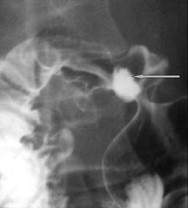

Aspect un ulcere jeune du

duodenum en TOGD mono contrast baryte avec

compression dosee . Image une niche ovalaire

remplisage par baryte avec etat oedemateuse de la

muqueuse peri lesionaire |